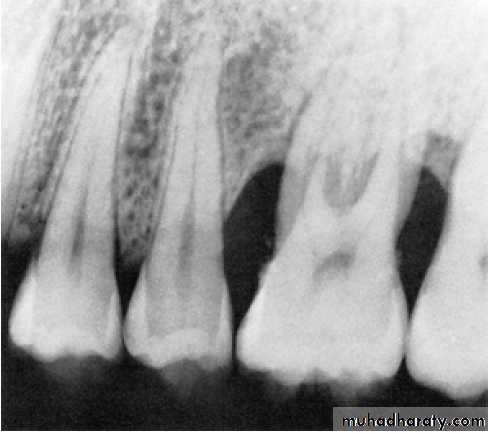

Pattern of bone loss:

Several investigators have analyzed the distance from the CEJ tothe alveolar crest.

The height of interdental bone may be reduced, with the crest perpendicular to the long axis of the adjacent teeth (horizontal bone loss), or

angular or arcuate defects (angular, or vertical, bone loss)

could form.

Parodontitis:

Parodontitis superficialis (mild –to- moderate periodontitis.

Parodontitis profunda (advanced periodontitis)

Parodontitis inter-radicularis (periodontitis in the furcation area).